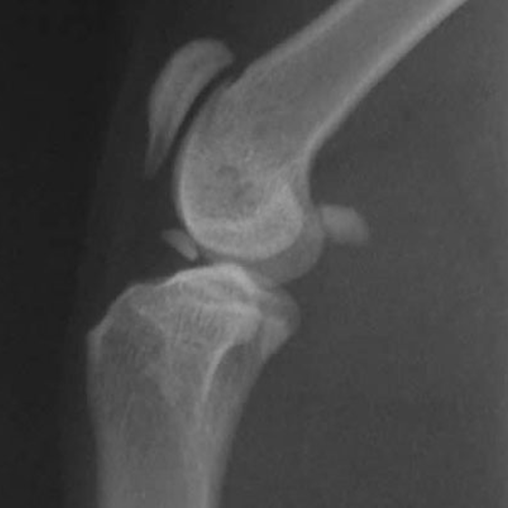

OCD in a cat